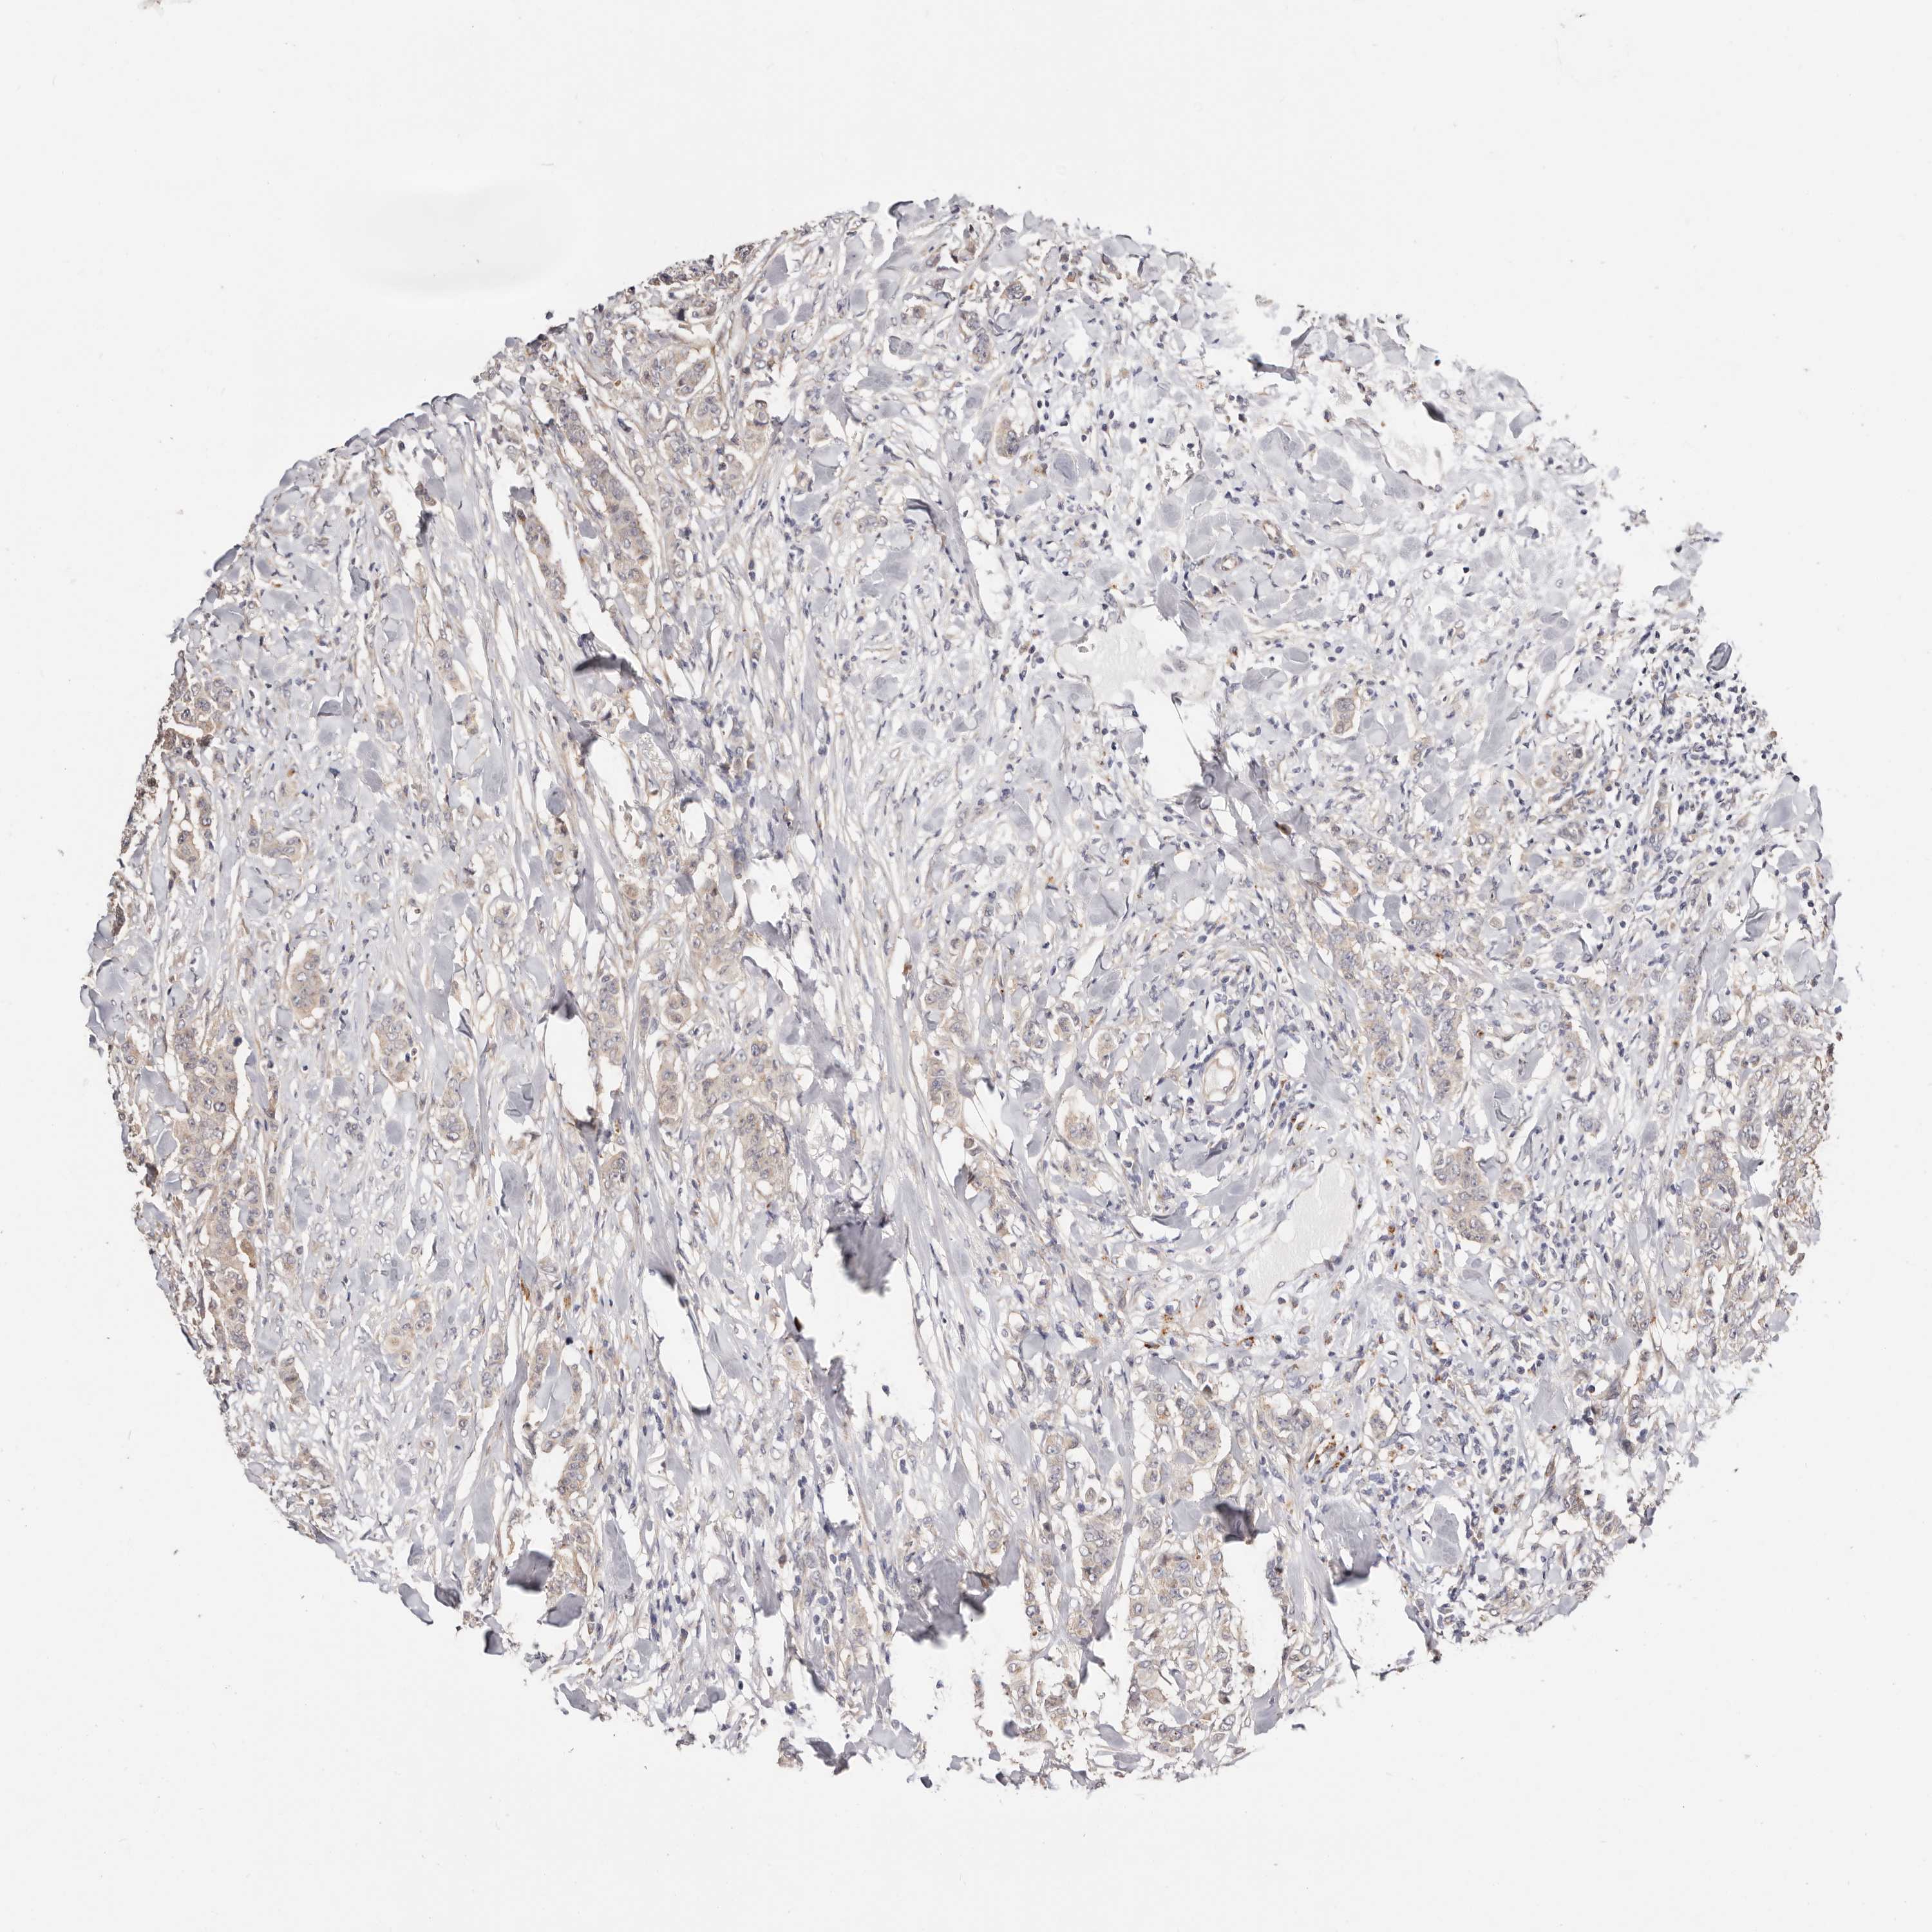

CANCER BREAST CANCER Show tissue menu

BRCA TCGA BRCA VALIDATION PROTEIN EXPRESSION

ANTIBODIES

AND

VALIDATION